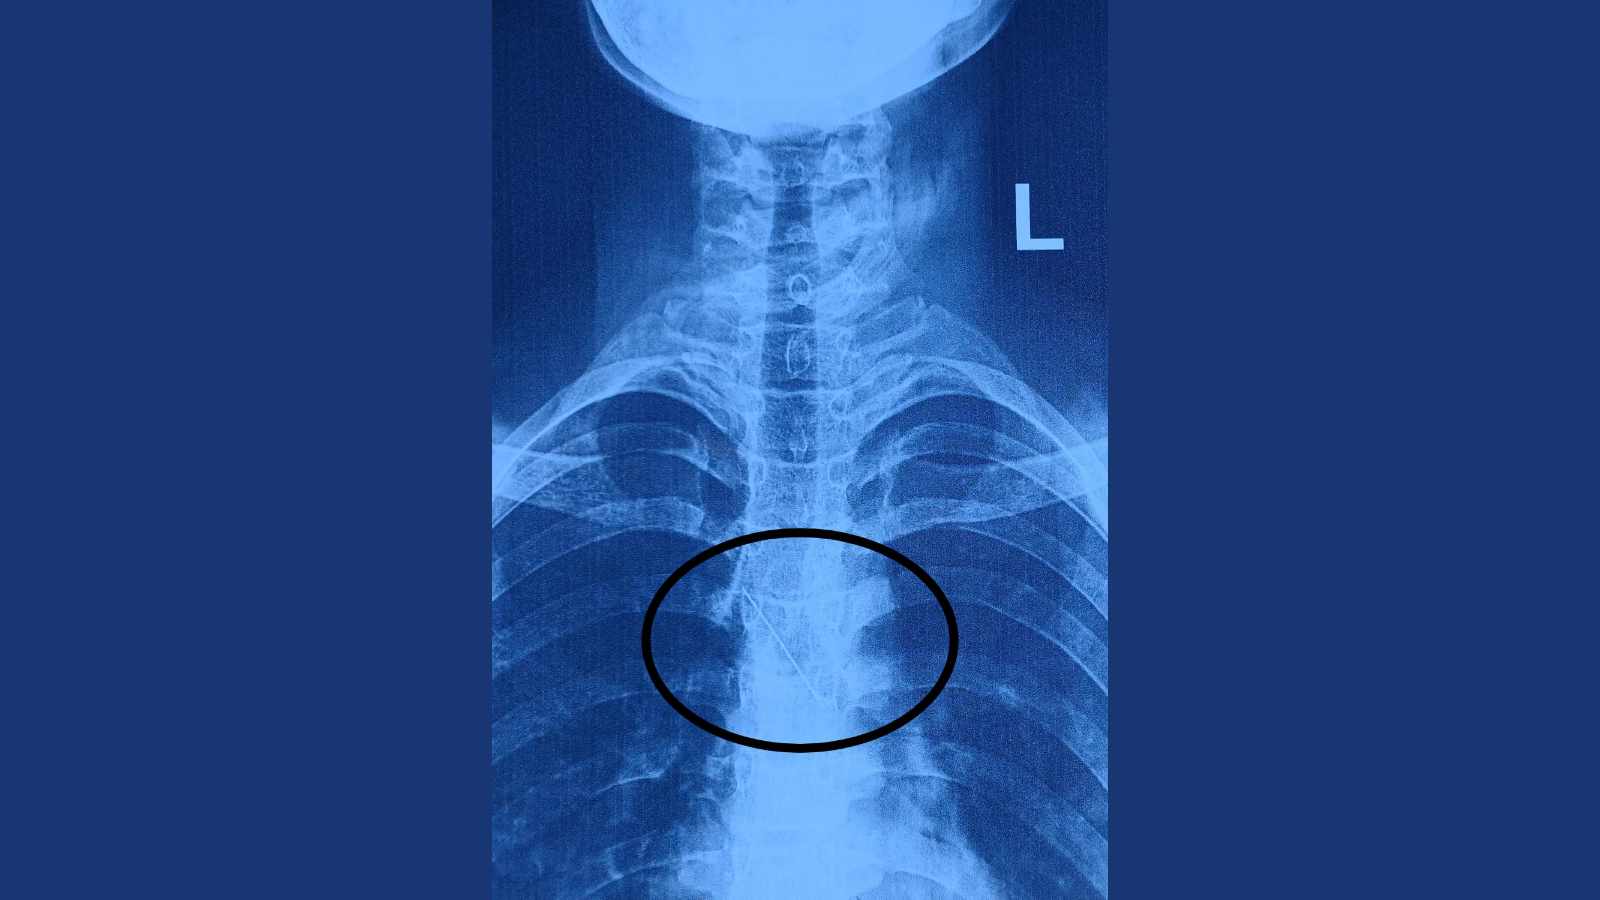

pin inside bronchusX-ray showed the metallic pin in the left main bronchus, very near the heart

He said the X-ray showed the metallic pin in the left main bronchus, very near the heart. The doctors admitted the patient and began the process for removal of the foreign body by rigid bronchoscopy and foreign body removal under general anaesthesia.

Dr Rahul Gupta of the ENT department removed the foreign body on the same day. “The pin was found to be in the left main bronchus and impinged on the right wall of the trachea near its lower end. The patient is admitted to the ENT and head-neck surgery department, and currently she is free from any dangerous respiratory complications,” a release from the hospital said.